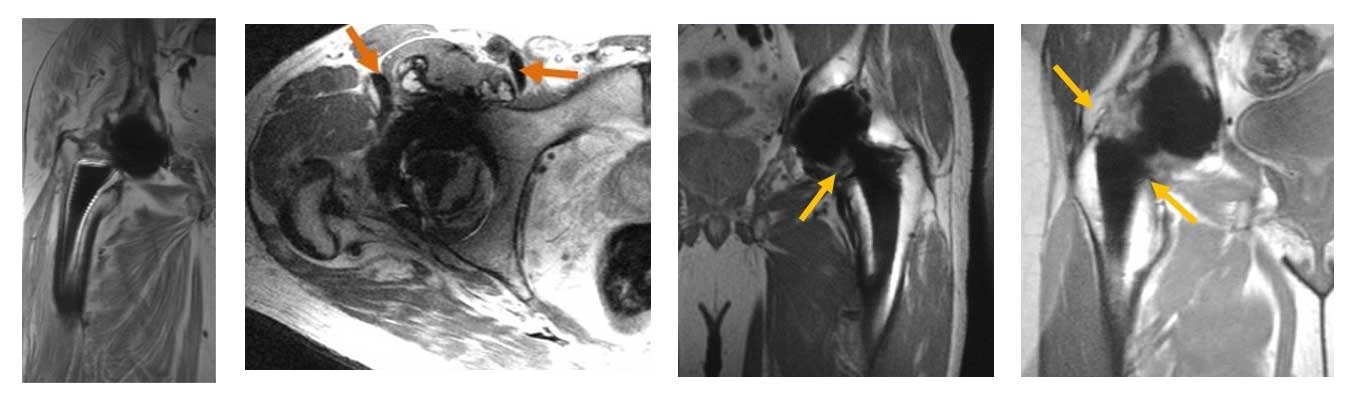

Advanced 3D multispectral imaging techniques permit visualization of soft tissues near total hip replacements. Left to Right: Image displays loosening of the femoral stem (bright lines around stem), metallic debris from implant wear (arrows), synovial response due to polymeric (plastic) wear debris from the implant (arrow), and an adverse local tissue reaction (arrows)